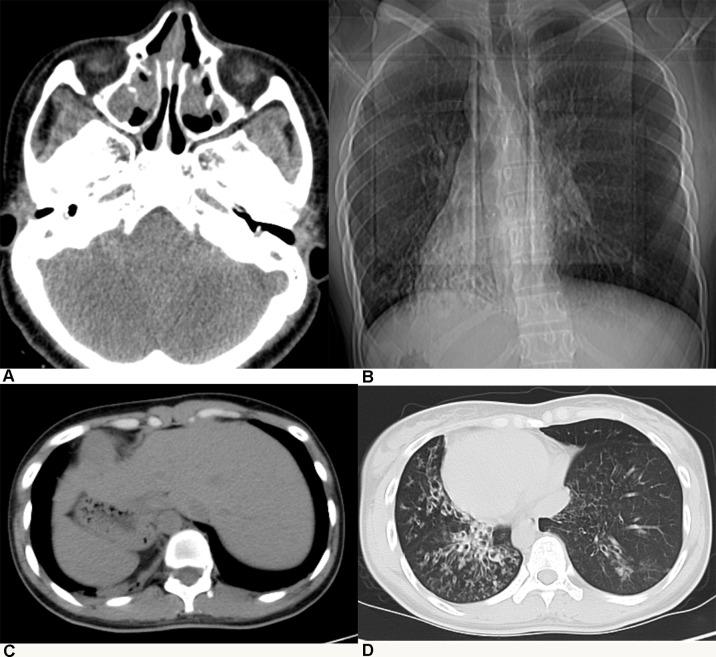

Primary ciliary dyskinesia (PCD), a rare genetic disorder, is mostly caused by defects in more than 40 known cilia structure-related genes. However, in approximately 20-35% of patients, it is caused by unknown genetic factors, and the inherited pathogenic factors are difficult to confirm. Kartagener syndrome (KTS) is a subtype of PCD associated with situs inversus, presenting more complex genetic heterogeneity. The aim of this study was to identify pathogenic mutations of candidate genes in Chinese patients with KTS and investigate the activation of the heterotaxy-related NOTCH pathway. Whole-exome sequencing was conducted in five patients with KTS. Pathogenic variants were identified using bioinformatics analysis. Candidate variants were validated by Sanger sequencing. The expression of the NOTCH pathway target genes was detected in patients with KTS. We identified 10 KTS-associated variants in six causative genes, namely, , , , , , and . Only one homozygote mutation was identified in (c.64dupT). Compound heterozygous mutations were found in and . Six novel mutations were identified in four genes. Further analyses showed that the NOTCH pathway might be activated in patients with KTS. Overall, our study showed that compound heterozygous mutations widely exist in Chinese KTS patients. Our results demonstrated that the activation of the NOTCH pathway might play a role in the situs inversus pathogenicity of KTS. These findings highlight that Kartagener syndrome might be a complex genetic heterogeneous disorder mediated by heterozygous mutations in multiple PCD- or cilia-related genes.

原发性纤毛运动障碍(PCD)是一种罕见的遗传性疾病,主要由40多个已知的纤毛结构相关基因缺陷引起。然而,在大约20%-35%的患者中,其病因是未知的遗传因素,且遗传致病因素难以确定。卡塔格内综合征(KTS)是PCD的一种亚型,与内脏反位有关,表现出更复杂的遗传异质性。本研究的目的是鉴定中国KTS患者候选基因的致病突变,并研究异位相关NOTCH通路的激活情况。对5例KTS患者进行了全外显子测序。使用生物信息学分析鉴定致病变异。通过桑格测序验证候选变异。检测了KTS患者中NOTCH通路靶基因的表达。我们在6个致病基因中鉴定出10个与KTS相关的变异,即 、 、 、 、 、 和 。仅在 (c.64dupT)中鉴定出1个纯合突变。在 和 中发现了复合杂合突变。在4个基因中鉴定出6个新突变。进一步分析表明,NOTCH通路可能在KTS患者中被激活。总体而言,我们的研究表明复合杂合突变在中国KTS患者中广泛存在。我们的结果表明,NOTCH通路的激活可能在KTS内脏反位的致病性中起作用。这些发现突出表明,卡塔格内综合征可能是一种由多个PCD或纤毛相关基因的杂合突变介导的复杂遗传异质性疾病。